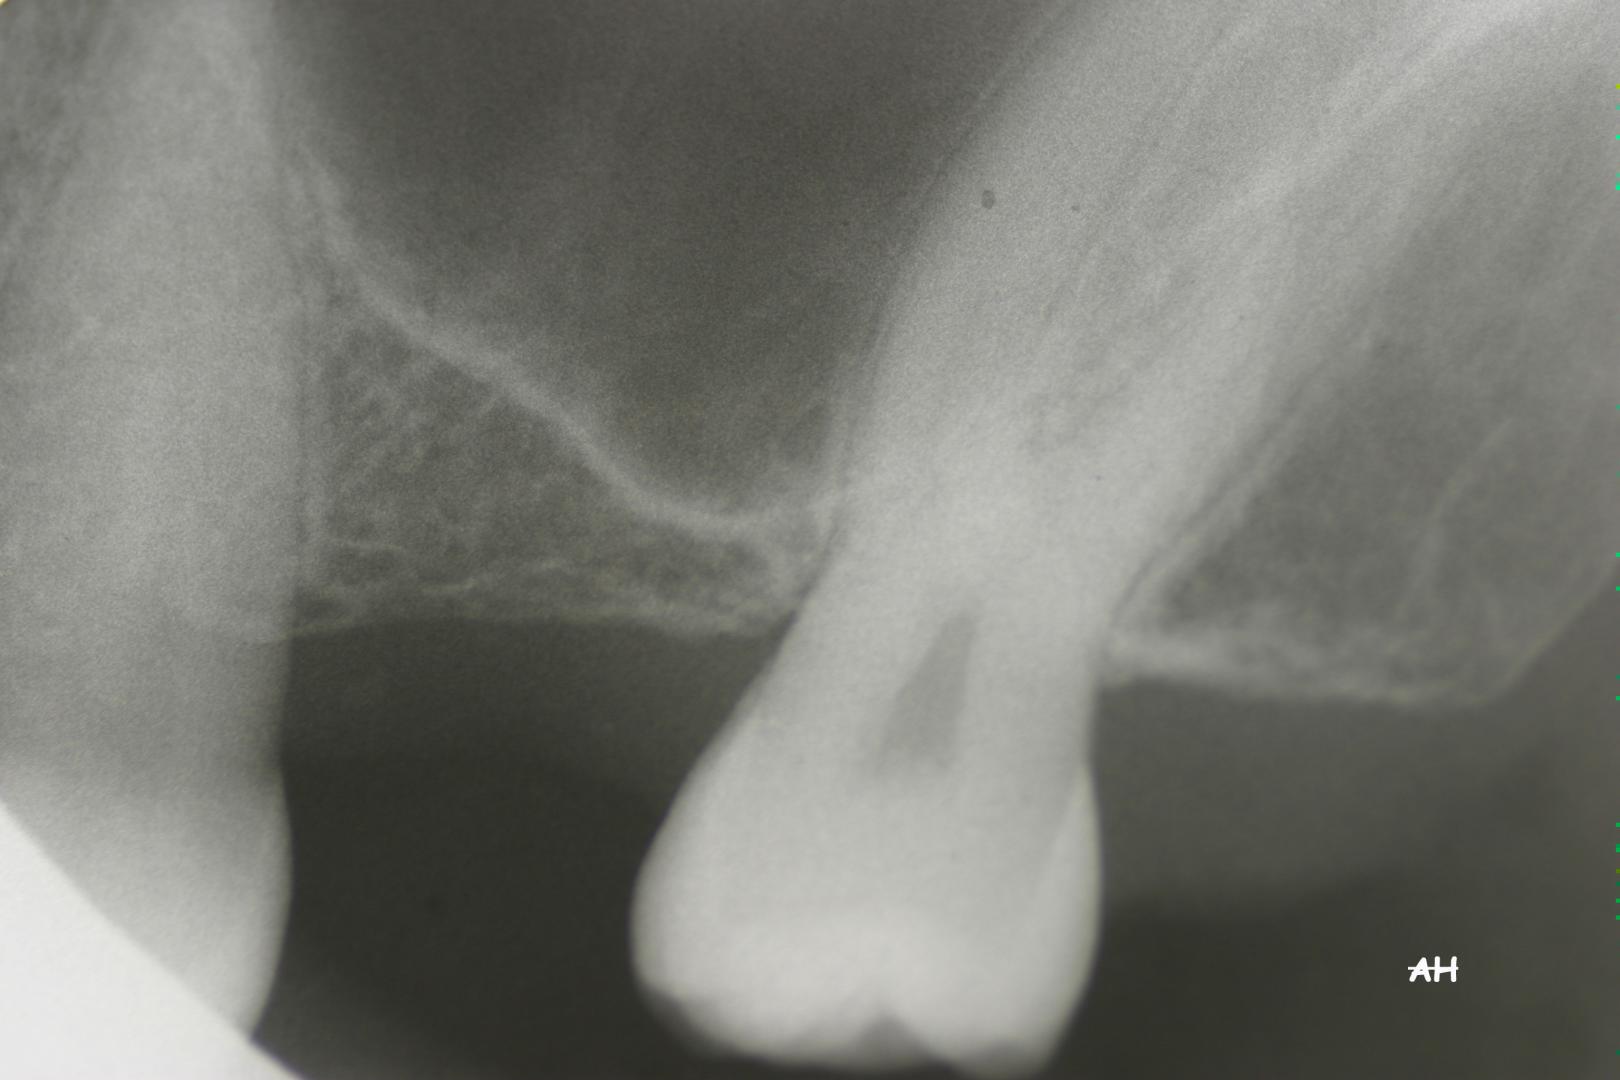

Exemple 12: Ici la pose de deux implants est envisagée, mais la hauteur d'os est insuffisante pour le deuxième implant. Le sinus (qui est une cavité creuse) est à moins de 6 mm de la surface de l'os. Idéalement il faudrait 10 mm d'os.

Exemple 12: Il faut donc relevé le sinus avec une greffe d'os avant de poser l'implant (Sinus lift).